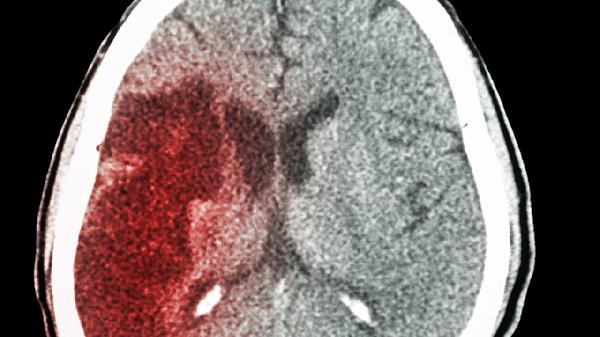

急性脑出血可能由高血压、脑血管畸形、脑动脉瘤、血液病、抗凝药物使用等因素引起。急性脑出血通常表现为突发剧烈头痛、呕吐、意识障碍、肢体偏瘫等症状,需立即就医处理。

长期未控制的高血压是急性脑出血最常见的原因。血压持续升高会导致脑内小动脉管壁变性坏死,形成微动脉瘤,在血压骤升时破裂出血。高血压脑出血好发于基底节区,患者可能出现对侧肢体偏瘫、言语不清等症状。治疗需紧急降压,常用药物包括乌拉地尔注射液、尼卡地平注射液等静脉降压药,同时需配合甘露醇注射液降低颅内压。